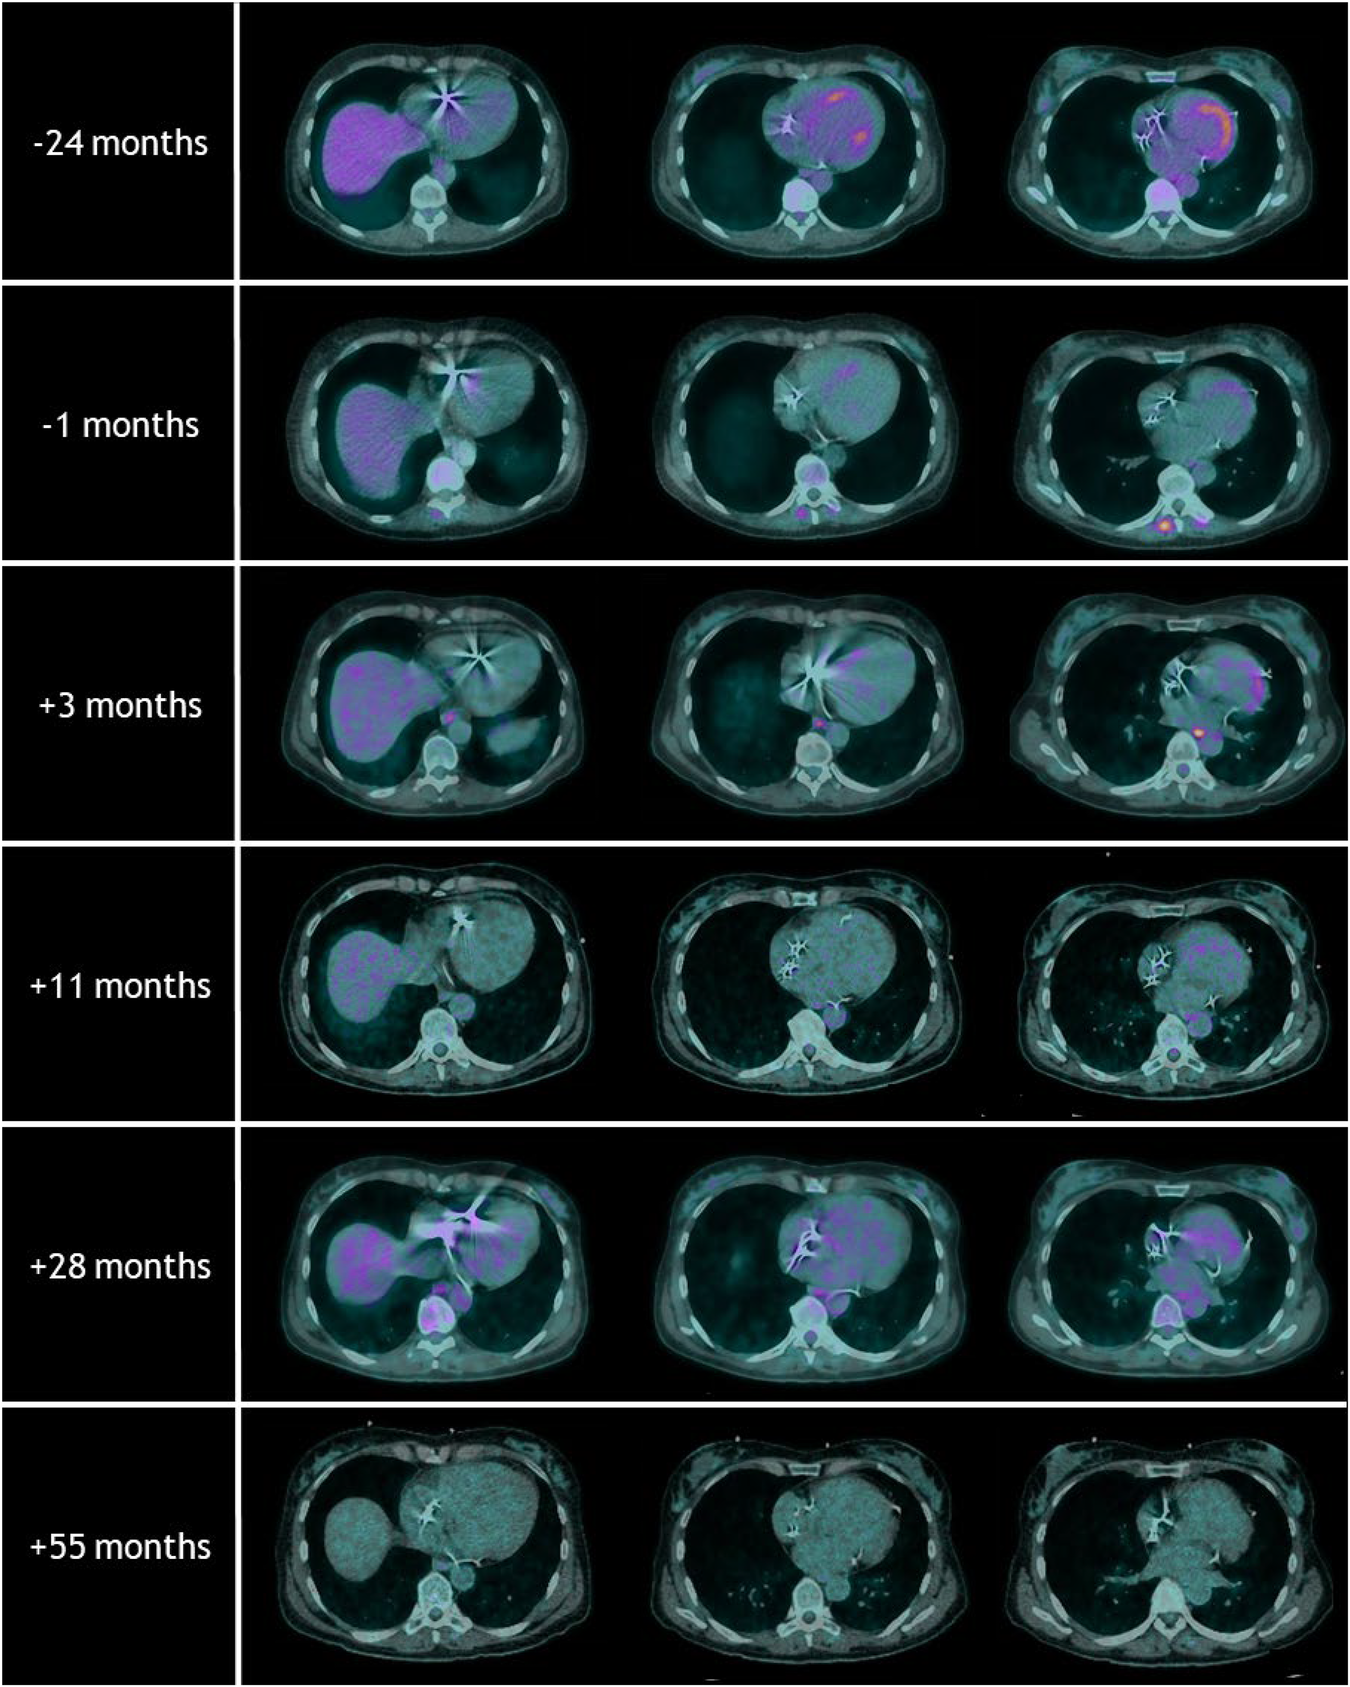

Figure 2 shows an overview of the repeated [18F]FDG-PET/CT scans. On the [18F]FDG-PET/CT scans prior to and 2 years before treatment, hypermetabolic areas of the anteroseptal segment and the posterior papillary muscle were observed. Three months after treatment, the hypermetabolic cardiac activity was reduced. Only in the basal anterior segment, corresponding to VT-PTV, a mild increase in metabolic activity was observed. Another [18F]FDG-PET/CT scan was performed 11 months after treatment and showed regression of this local hypermetabolic activity and no new pathological activity. The [18F]FDG-PET/CT scan at 55 months did not show any signs of active cardiac sarcoidosis, and a state of remission was achieved.

Figure 2

Overview of the repeated [18F]FDG-PET/CT scans with the timing relative to radiotherapy treatment. Note the hypermetabolic areas of the anteroseptal segments at the [18F]FDG-PET/CT scans prior to and 24 months before radiotherapy. Follow-up [18F]FDG-PET/CT scans after radiotherapy showed regression of these local hypermetabolic areas. The [18F]FDG-PET/CT scan at 55 months did not show any signs of active cardiac sarcoidosis.